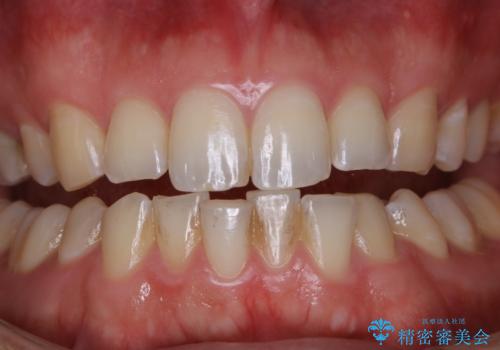

コーヒーの着色落としをPMTCでキレイに

- コーヒが好きで、ステインが付くことが気になるとのことで来院されました。PMTC30分コースを行いました。

トリートメントでは、歯の表面にミネラルや栄養分を補給します。

定期的に専門的な機械や材料を使用してのクリーニングを行うことで、歯質の強化になり、ステインや汚れが付きにくい状態となります。